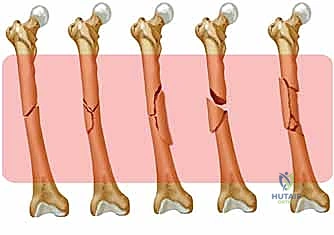

من بين أحدث وأبرز هذه التقنيات المتقدمة يبرز إجراء "تثبيت كسر عظم الفخذ بالمسامير النخاعية الارتدادية" (Retrograde Nailing). يمثل هذا الإجراء المبتكر ثورة حقيقية في طب جراحة العظام، حيث يتم إدخال مسمار معدني مصمم هندسياً (مصنوع غالباً من التيتانيوم لتوافقه الحيوي) داخل التجويف النخاعي للعظم. وما يميز الطريقة "الارتدادية" هو أن نقطة الدخول تبدأ من الركبة وتتجه للأعلى نحو الحوض، عكس الطريقة التقليدية (التقدمية) التي تبدأ من الورك للأسفل. تُعد هذه التقنية خياراً استراتيجياً ومثالياً للعديد من الحالات المعقدة، مثل كسور الثلث السفلي من الفخذ، المرضى الذين يعانون من السمنة المفرطة، أو المصابين بكسور متعددة (Polytrauma).

ضمن الخيارات الجراحية، توجد الشرائح والمسامير (Plates and Screws) أو المسامير النخاعية (Intramedullary Nails). تُعد المسامير النخاعية هي الخيار الأفضل لمعظم كسور جسم الفخذ لأنها توفر تثبيتاً في مركز العظم (ميكانيكا حيوية أفضل لتقاسم الحمل بدلاً من تحمل الحمل بالكامل مثل الشرائح)، وتتطلب شقوقاً جراحية أصغر، مما يحافظ على التروية الدموية الحيوية لالتئام الكسر.

ما هو التثبيت بالمسمار النخاعي الارتدادي؟ ولماذا يُفضل في بعض الحالات؟

المسمار النخاعي هو قضيب معدني طويل (مصنوع من التيتانيوم أو الفولاذ المقاوم للصدأ الخاص بالطب) يتم إدخاله داخل التجويف النخاعي الأجوف لعظم الفخذ. يعمل هذا المسمار كجبيرة داخلية قوية جداً تدعم العظم المكسور من الداخل.

الفرق بين المسمار التقدمي (Antegrade) والمسمار الارتدادي (Retrograde):